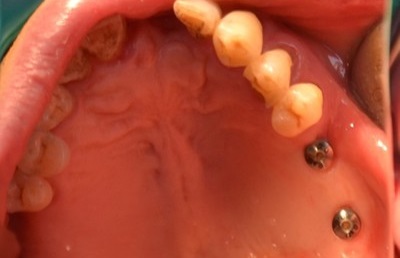

치주질병이나 잇몸 염이 자주 발생할 수 있어 잇몸 관리와 병행하는 사례도 많은 편이죠. 이처럼 어금니가 소실되면 정상적인 저작 기능이 힘들어 식사하는데 매우 큰 불편함을 느낄 수 있습니다. 이 경우 임플란트를 통해 자연 치아에 가까운 씹는 힘과 형태를 되찾을 수 있으며 저작 능력이 강조되는 어금니를 대체하는데 있어 어금니임플란트는 가장 효율적인 관리라고 볼 수 있습니다.

오스템 임플란트 CA, BA 제품 및 오스템 A-Oss, 오스템 Ossguide를 통해 만족도 높은 결과를 확인하실 수 있습니다.